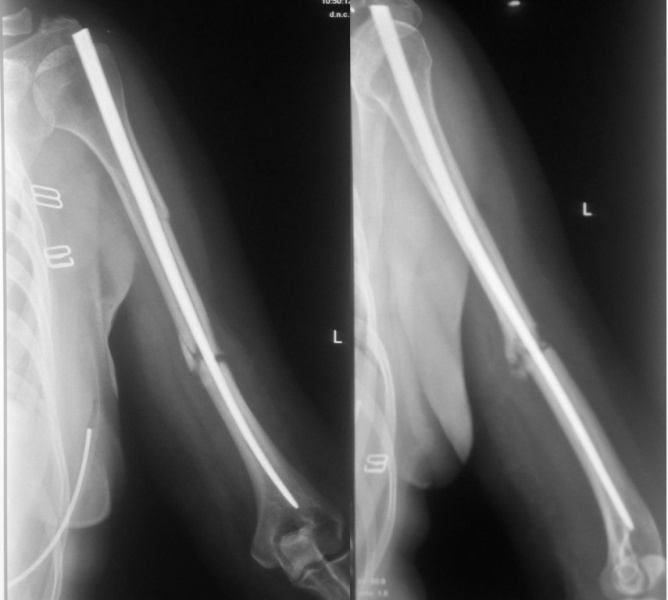

[Ortho] Псевдоартроз н/3 плеча после реЗИМО

Вот снимки от 17.08.2016, максимально приближенные из имеющихся по дате

к реостеосинтезу!